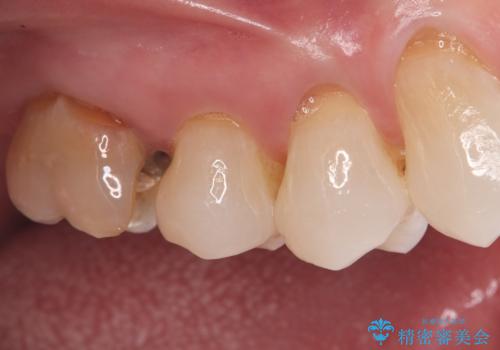

- 「奥歯の詰め物が取れた」という主訴でご来院されました。レントゲンおよび視診の結果、詰め物が外れた内部で虫歯が再発しており、根の先にも炎症が見られたため、再根管治療(根の再治療)が必要と診断しました。 特に上顎の大きな奥歯(第一大臼歯)は、通常の根管以外に「MB2」と呼ばれる隠れた根管が存在することが多く、これが未処置のままだと再発の原因となります。そこで、歯科用顕微鏡(マイクロスコープ)を用いて徹底的に内部を清掃し、その後、強度と審美性に優れたオールセラミッククラウンで修復する計画を立案しました。

顕微鏡によるMB2の発見: 歯科用顕微鏡(マイクロスコープ)を使用し、根管内を強拡大して観察したところ、事前の予想通り、従来の治療では見逃されていた**第4の根管「MB2」**を発見しました。この未処置だった根管内の汚れを徹底的に除去・消毒することで、痛みの再発リスクを根本から取り除きました。